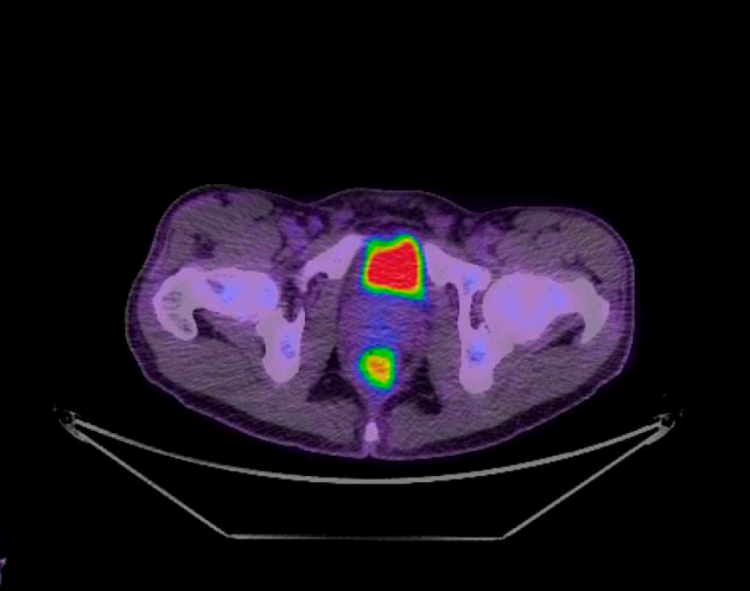

New study shows smarter scans help blood cancer patients

06 July 2022

The randomised multicentre trial found patients who were given a combination FDG-PET/CT scan instead of a conventional CT scan were able to be given more targeted treatments.